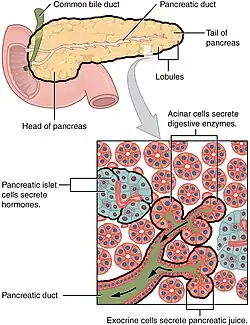

O cancro (português europeu) ou câncer (português brasileiro) do pâncreas surge quando as células do pâncreas, um órgão glandular atrás do estômago, se começam a multiplicar de forma descontrolada e formam um tumor. Estas células cancerígenas têm a capacidade de invadir outras partes do corpo.[10] Existem diversos tipos de cancro do pâncreas. O mais comum, adenocarcinoma pancreático, corresponde a aproximadamente 85% dos casos e em muitas situações o termo "cancro do pâncreas" é usado para designar apenas este tipo. Estes adenocarcinomas começam-se a formar na parte do pâncreas que produz as enzimas digestivas. A partir destas células podem também surgir vários outros tipos de cancro, que no conjunto representam a maioria dos não-adenocarcinomas. Um a dois em cada 100 casos de cancro do pâncreas são tumores neuroendócrinos que se formam a partir das células do pâncreas produtoras de hormonas. Este tipo é geralmente menos agressivo que o adenocarcinoma pancreático.[2]

Os diversos tipos de cancro do pâncreas podem ser divididos em dois grupos genéricos. A grande maioria dos casos (99%) ocorre na parte do pâncreas que produz enzimas digestivas, denominada de componente exócrino. Embora existam vários subtipos de cancros pancreáticos exócrinos, o diagnóstico e tratamento é em grande parte idêntico. A pequena minoria de cancros que surge no tecido produtor de hormonas (endócrino) apresenta características clínicas diferentes. Ambos os grupos ocorrem principalmente (mas não de forma exclusiva) em pessoas com mais de 40 anos e são ligeiramente mais comuns em homens. No entanto, alguns subtipos mais raros ocorrem principalmente em mulheres ou crianças.[16][17]

Cancros exócrinos

O grupo exócrino é dominado pelo adenocarcinoma pancreático, também denominado "invasivo" ou "ductal", que é de longe o tipo mais comum e corresponde a cerca de 85% de todos os cancros pancreáticos.[2] Por outro lado, o tecido a partir do qual se forma, o epitélio ductal pancreático, representa apenas 10% do volume de células do pâncreas.[18] Este cancro tem origem nos ductos que transportam determinadas hormonas e enzimas para fora do pâncreas. Cerca de 60–70% dos adenocarcinomas ocorrem na cabeça do pâncreas (ver diagrama à direita).[2]

O segundo tipo mais comum, o carcinoma de células acinares, tem origem nos aglomerados de células que produzem estas enzimas e corresponde a 5% de todos os cancros pancreáticos exócrinos. Os carcinomas de células acinares podem causar sobreprodução de determinadas moléculas, neste caso de enzimas digestivas, que podem provocar sintomas como irritações cutâneas ou dores nas articulações. Os cistoadenocarcinomas correspondem a 1% dos cancros pancreáticos e apresentam melhor prognóstico do que os restantes tipos exócrinos.[19]

A pequena minoria de tumores que se forma nas restantes áreas do pâncreas são sobretudo tumores neuroendócrinos do pâncreas (PanNET).[22] Os tumores neuroendócrinos (NET) são um grupo diversificado de tumores benignos ou malignos que se forma nas células neuroendócrinas, as quais são responsáveis pela integração do sistema nervoso e endócrino. Os NET podem formar-se na maior parte dos órgãos, incluindo o pâncreas, embora todos os tipos malignos sejam considerados raros. Os PanNET são agrupados em de tipo "funcional" e "não funcional", dependendo do grau de produção de hormonas. Os de tipo funcional segregam para a corrente sanguínea hormonas como a insulina, gastrina e glicagina, muitas vezes em grande quantidade, dando origem a sintomas graves como pouco açúcar no sangue, embora também favoreçam a deteção precoce da doença. Os PanNET mais comuns são os insulinomas e os gastrinomas, assim denominados de acordo com as hormonas que segregam. Os de tipo não funcional não segregam hormonas em quantidade suficiente para provocar sintomas clínicos visíveis. Por esta razão, muitas vezes os PanNET de tipo não funcional só são diagnosticados depois do cancro se ter disseminado para outras partes do corpo.[23]